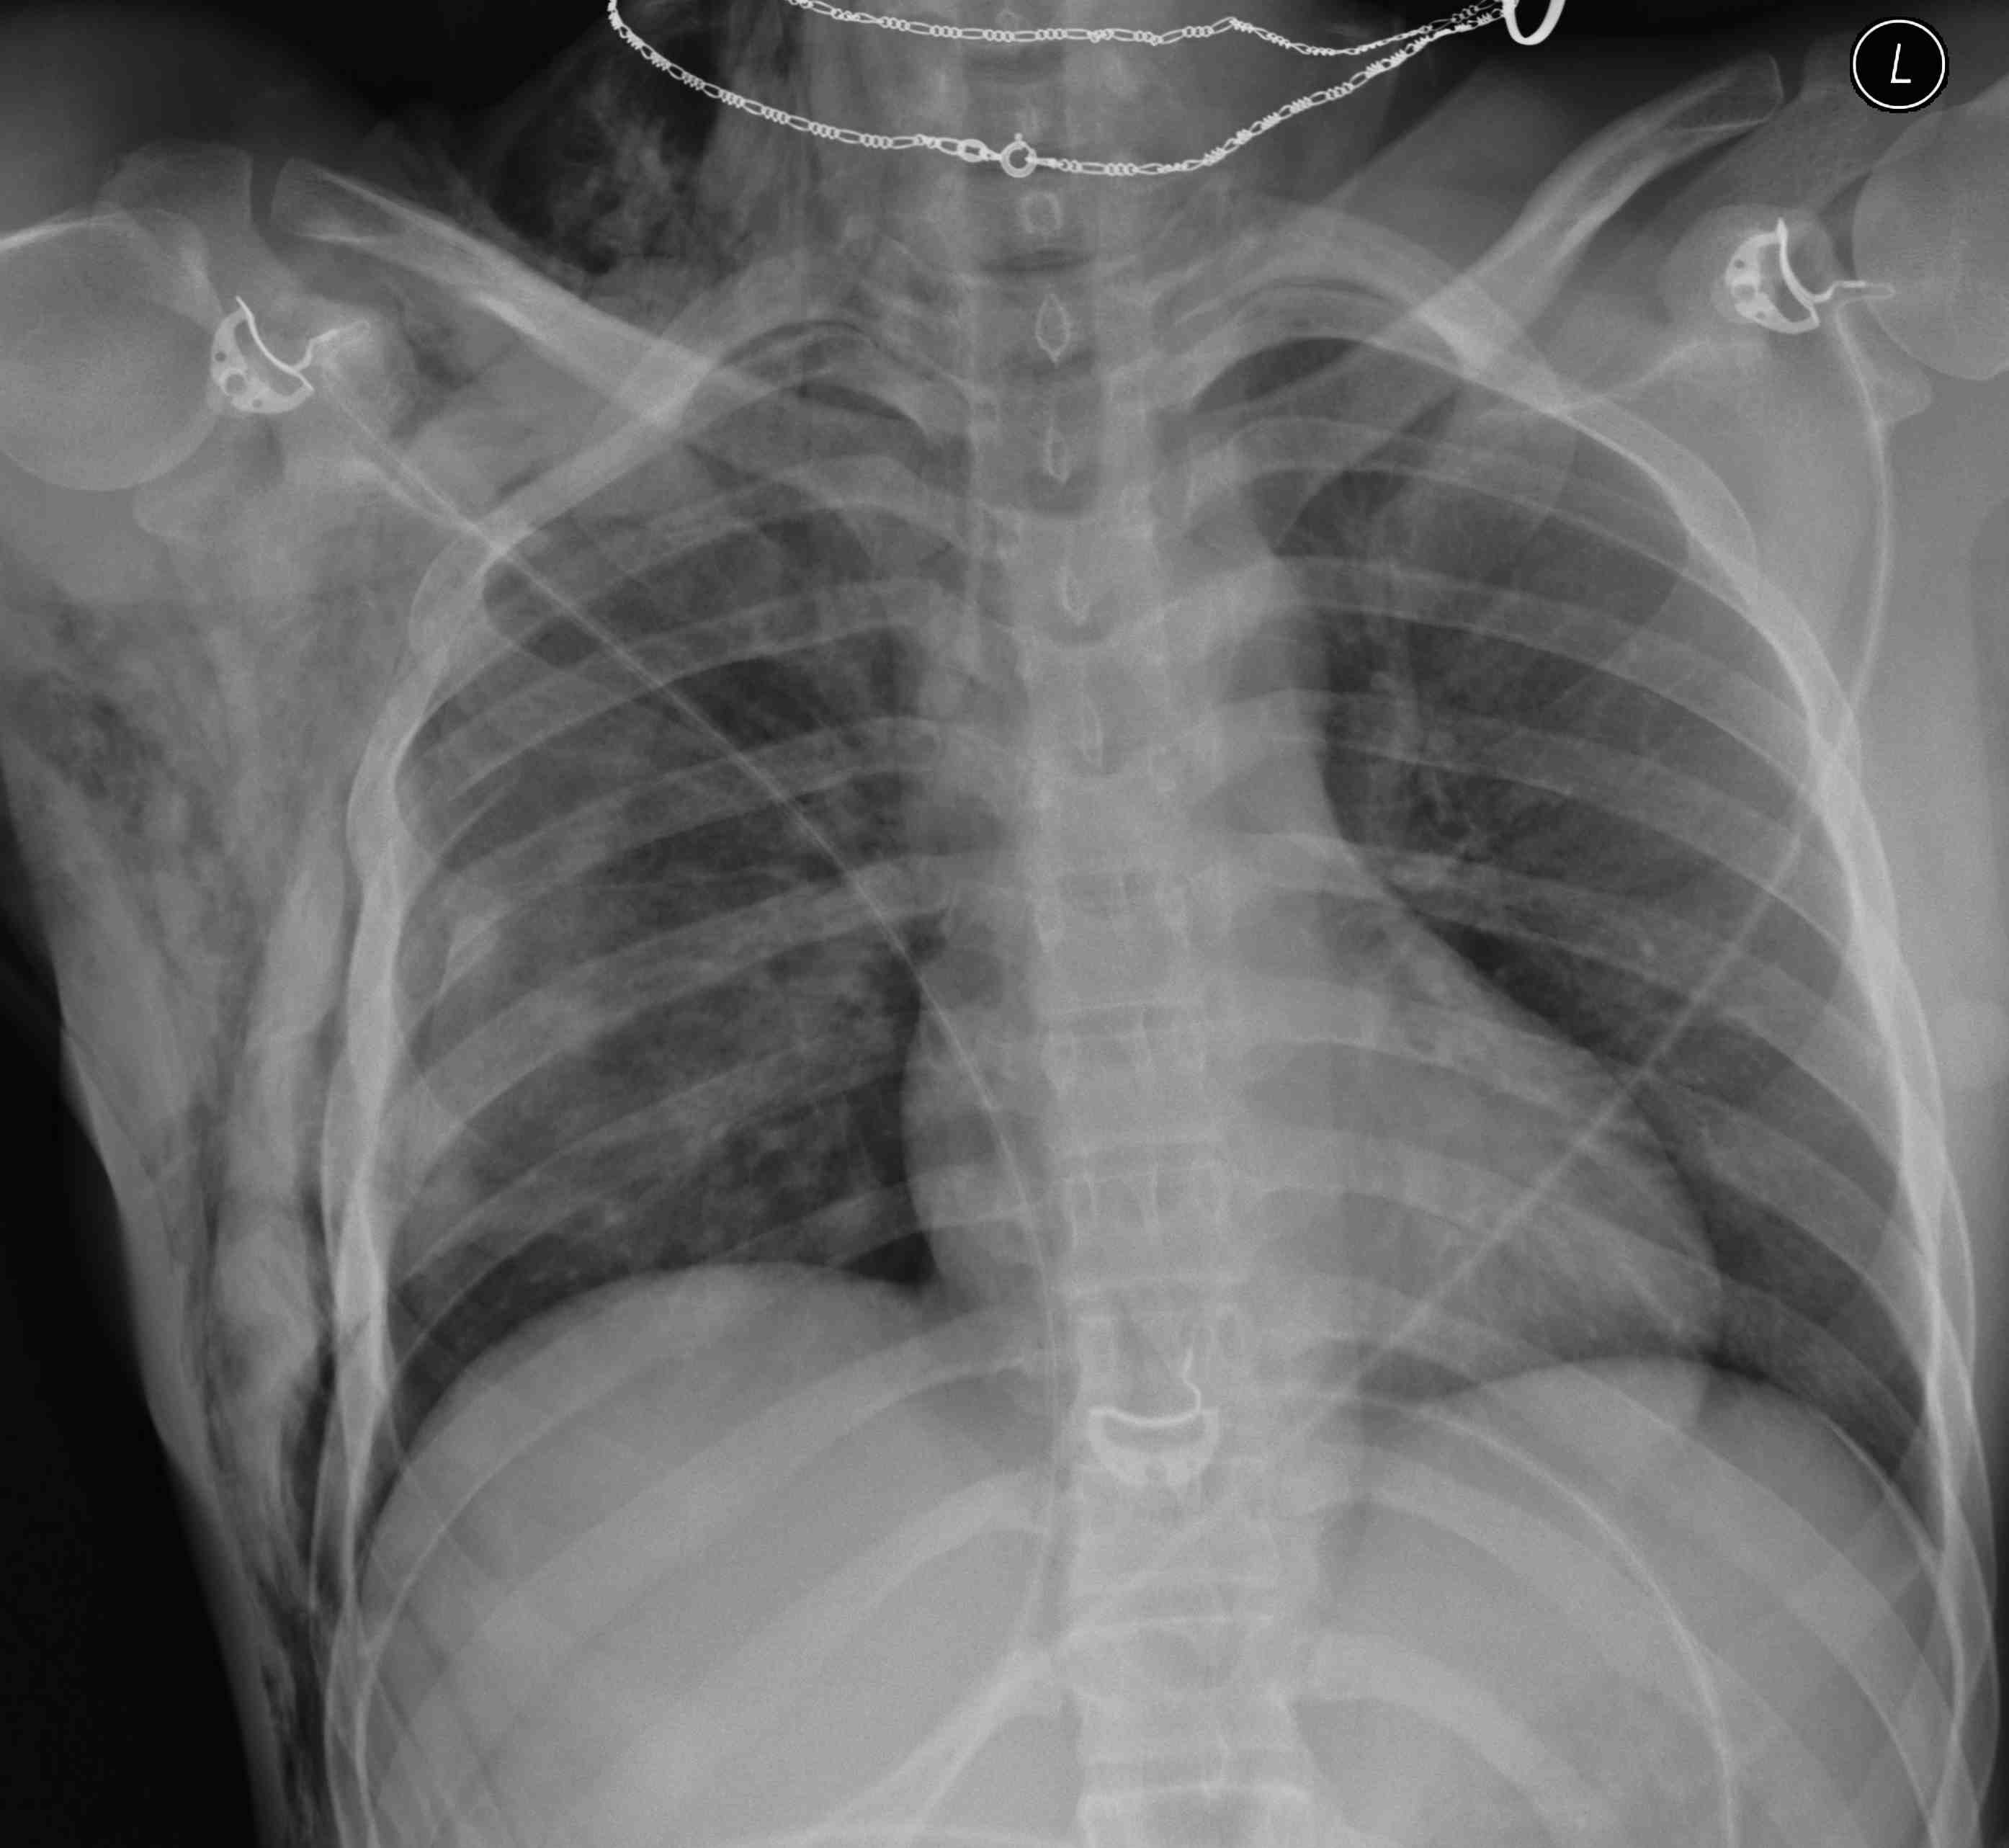

Pneumothorax / haemothorax

- decreased breath sounds

Tension pneumothorax

- heart apex and trachea displaced

- heart sounds (muffled + distended neck veins = cardiac tamponade)

- CXR (hemothorax / widened mediastinum)

Trauma Series

- lateral C spine / CXR / AP pelvis